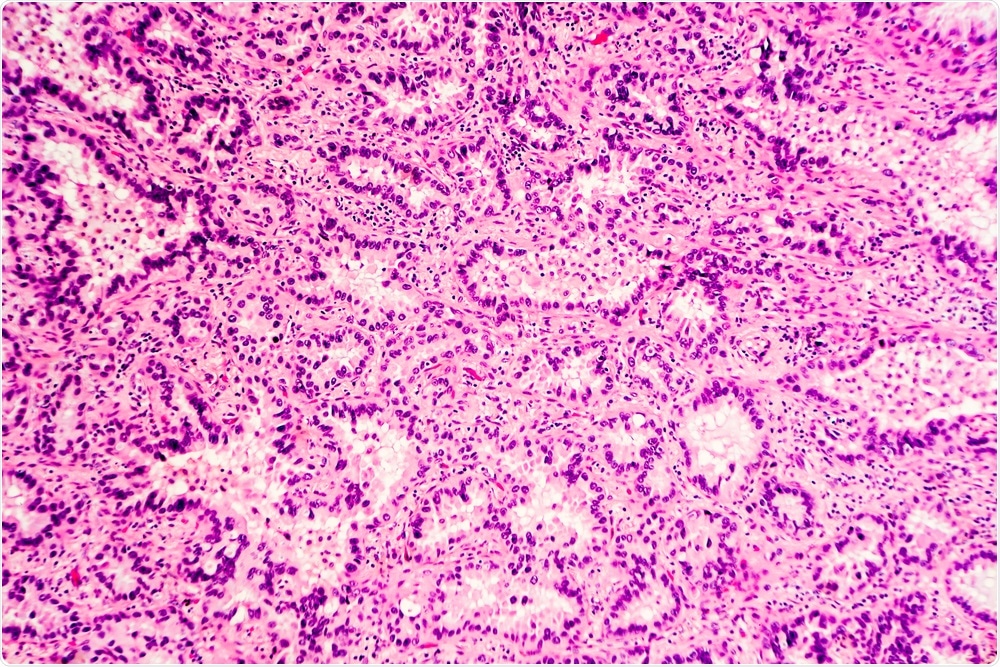

H&E stain of lung adenocarcinoma. (Image Credit: David A. Litman/Shutterstock.com)H&E stain of lung adenocarcinoma. (Image Credit: David A. Litman/Shutterstock.com)